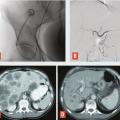

Les tumeurs neuro-endocrines sont relativement rares, avec une incidence de 5/100 000.16 Elles provien- nent de différents types de cellules neuro-endocrines qui ne sont pas uniquement présentes dans les glandes endocrines mais aussi dans de nombreux tissus, avec une prédominance dans le poumon dans 30 % des cas, et le système digestif, principalement le pancréas et le tube digestif creux dans 36 % des cas. Pour l’appareil digestif, ces tumeurs sont souvent découvertes à un stade avancé, avec des métastases hépatiques multiples. Les traitements ciblés sont privilégiés lorsque les tumeurs sont bien différenciées. En cas de tumeurs peu différenciées, les patients ayant des métastases peu nombreuses peuvent être traités par une chirurgie de résection ou par ablathermie, et les patients ayant une maladie diffuse par chimio- embolisation (fig. 4 ) ou injection de particules radioactives, sans consensus actuellement en raison de la taille limitée des séries. Là aussi, la décision est prise en réunion de concertation multidisciplinaire.